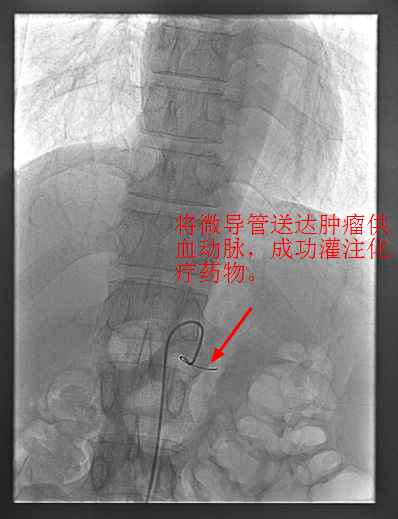

近期内三科主任李旭丹與影像科副主任胡志華攜手開展DSA下灌注化療術,治療一例局部晚期胰腺癌患者,成功将高濃度化療藥物經腫瘤的供血動脈注入到腫瘤組織中。經治療後,患者恢複良好,現已順利出院。該技術能使腫瘤組織藥物濃度達到傳統治療的10倍左右,具有殺滅腫瘤組織能力強,全身毒副作用小等優點。

4月30日下午,李旭丹主任與胡志華主任上台實施介入化療術,在DSA造影下,清晰可見胰腺腫瘤的供血動脈,專家們将微導管經股動脈穿刺送達瘤體的供血動脈,成功将化療藥物灌注至瘤體,順利完成手術。術後,患者症狀明顯好轉,并于5月4日順利出院。

李旭丹主任介紹,介入灌注化療,因其能準确定位腫瘤供血動脈,将藥物直接送達瘤體,能更好殺滅癌細胞,且副作用小,在胰腺癌的治療中有着非常明顯的優勢,能爲患者赢得更多的生存機會。